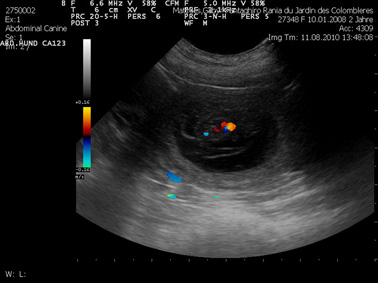

Wir waren am 11. August 2010 mit Rania bei unserer Tierärztin zur Ultraschalluntersuchung. Auf dem Bild sieht man einen Fötus. Die Farben zeigen die Herzaktivität.